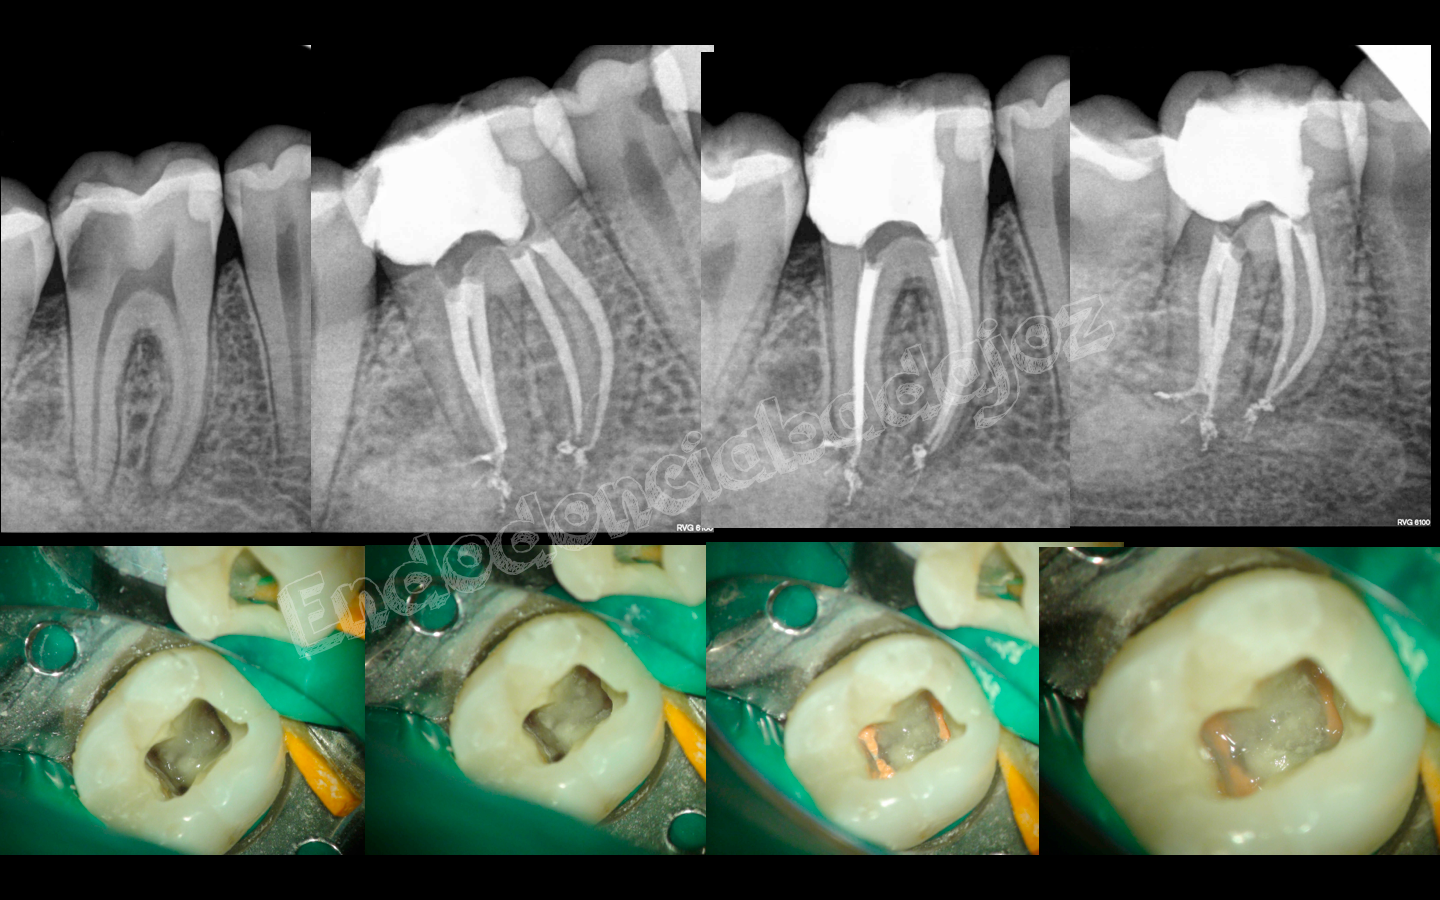

Después de una temporada sin postear ningún caso, hoy me levanté con ganas de publicar alguno, se trata de cinco casos, a mi juicio, interesantes, cuatro endodoncias de molares inferiores con anatomías complicadas y un retratamiento de un molar superior . Espero que os gusten.

Captura de pantalla 2013-05-07 a la(s) 10.07.50

Captura de pantalla 2013-05-07 a la(s) 10.07.57

Captura de pantalla 2013-05-07 a la(s) 10.08.01

Captura de pantalla 2013-05-07 a la(s) 10.08.03